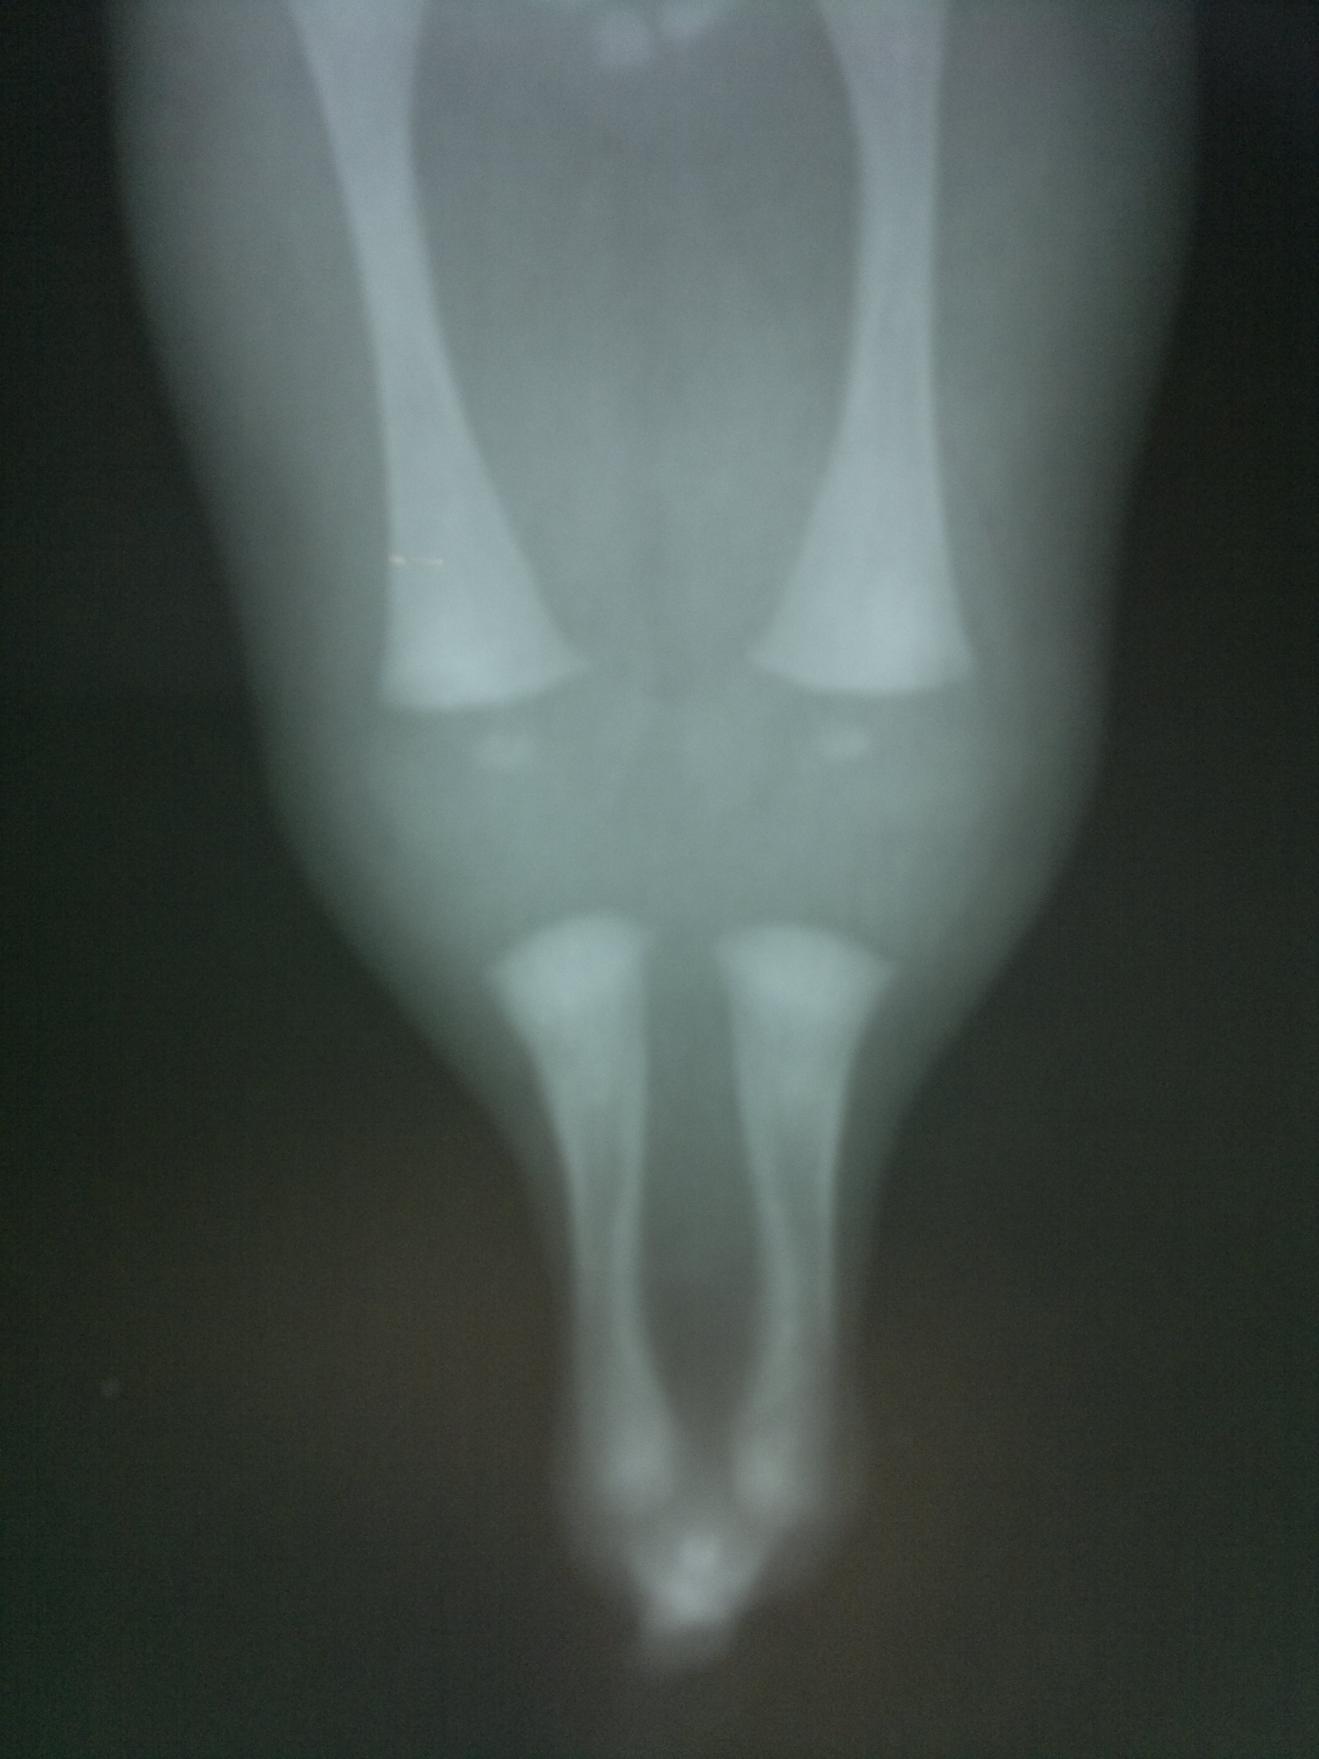

Dado la letalidad es importante realizar estudios radiológicos y anatomopatológicos que permitan confirmar el cuadro.

Figura 2.8.4. Sirenomelia. (4 imágenes)